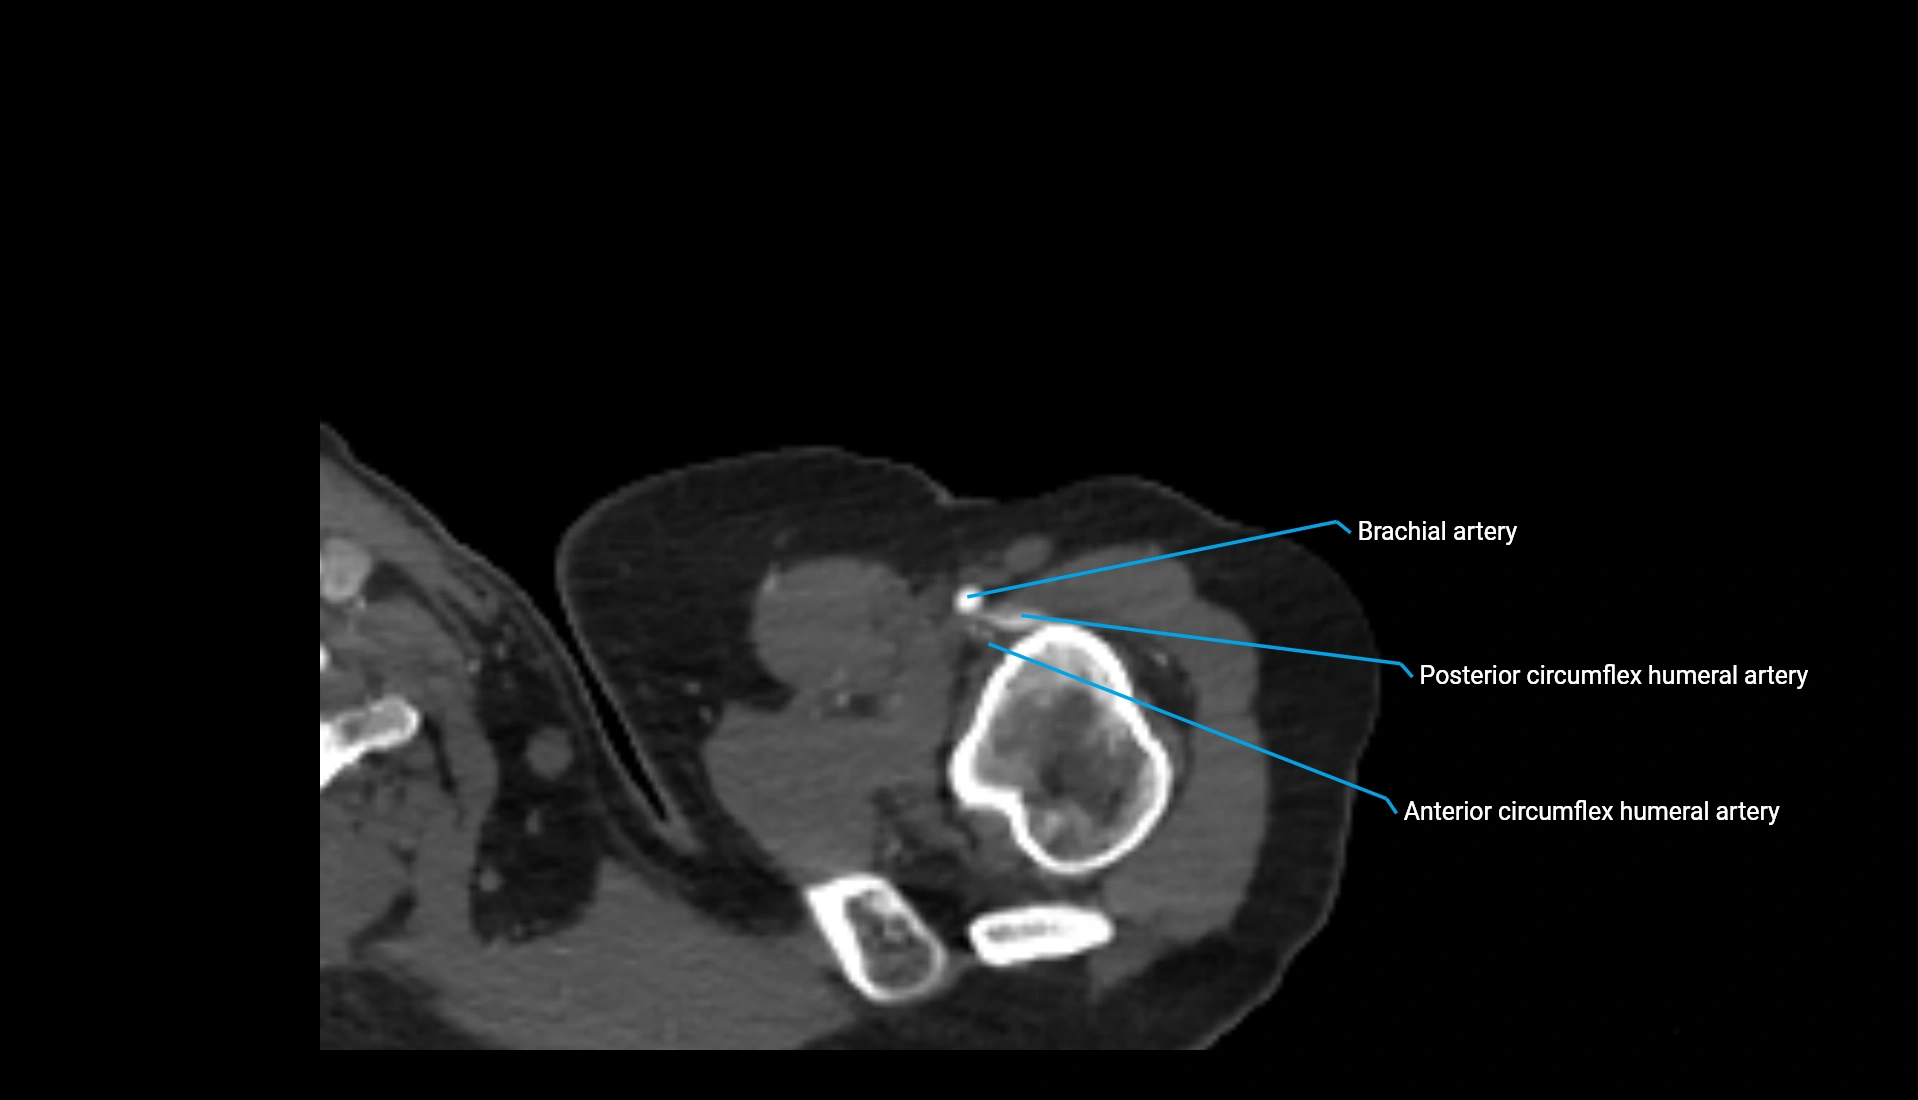

CT Appearance

Non-Contrast CT:

• Cortex: High-density, sharply defined

• Subchondral bone: Dense cancellous matrix

• Articular surface: Smooth concave contour articulating with the capitellum

• Excellent for evaluating bone integrity, alignment, and subtle fractures